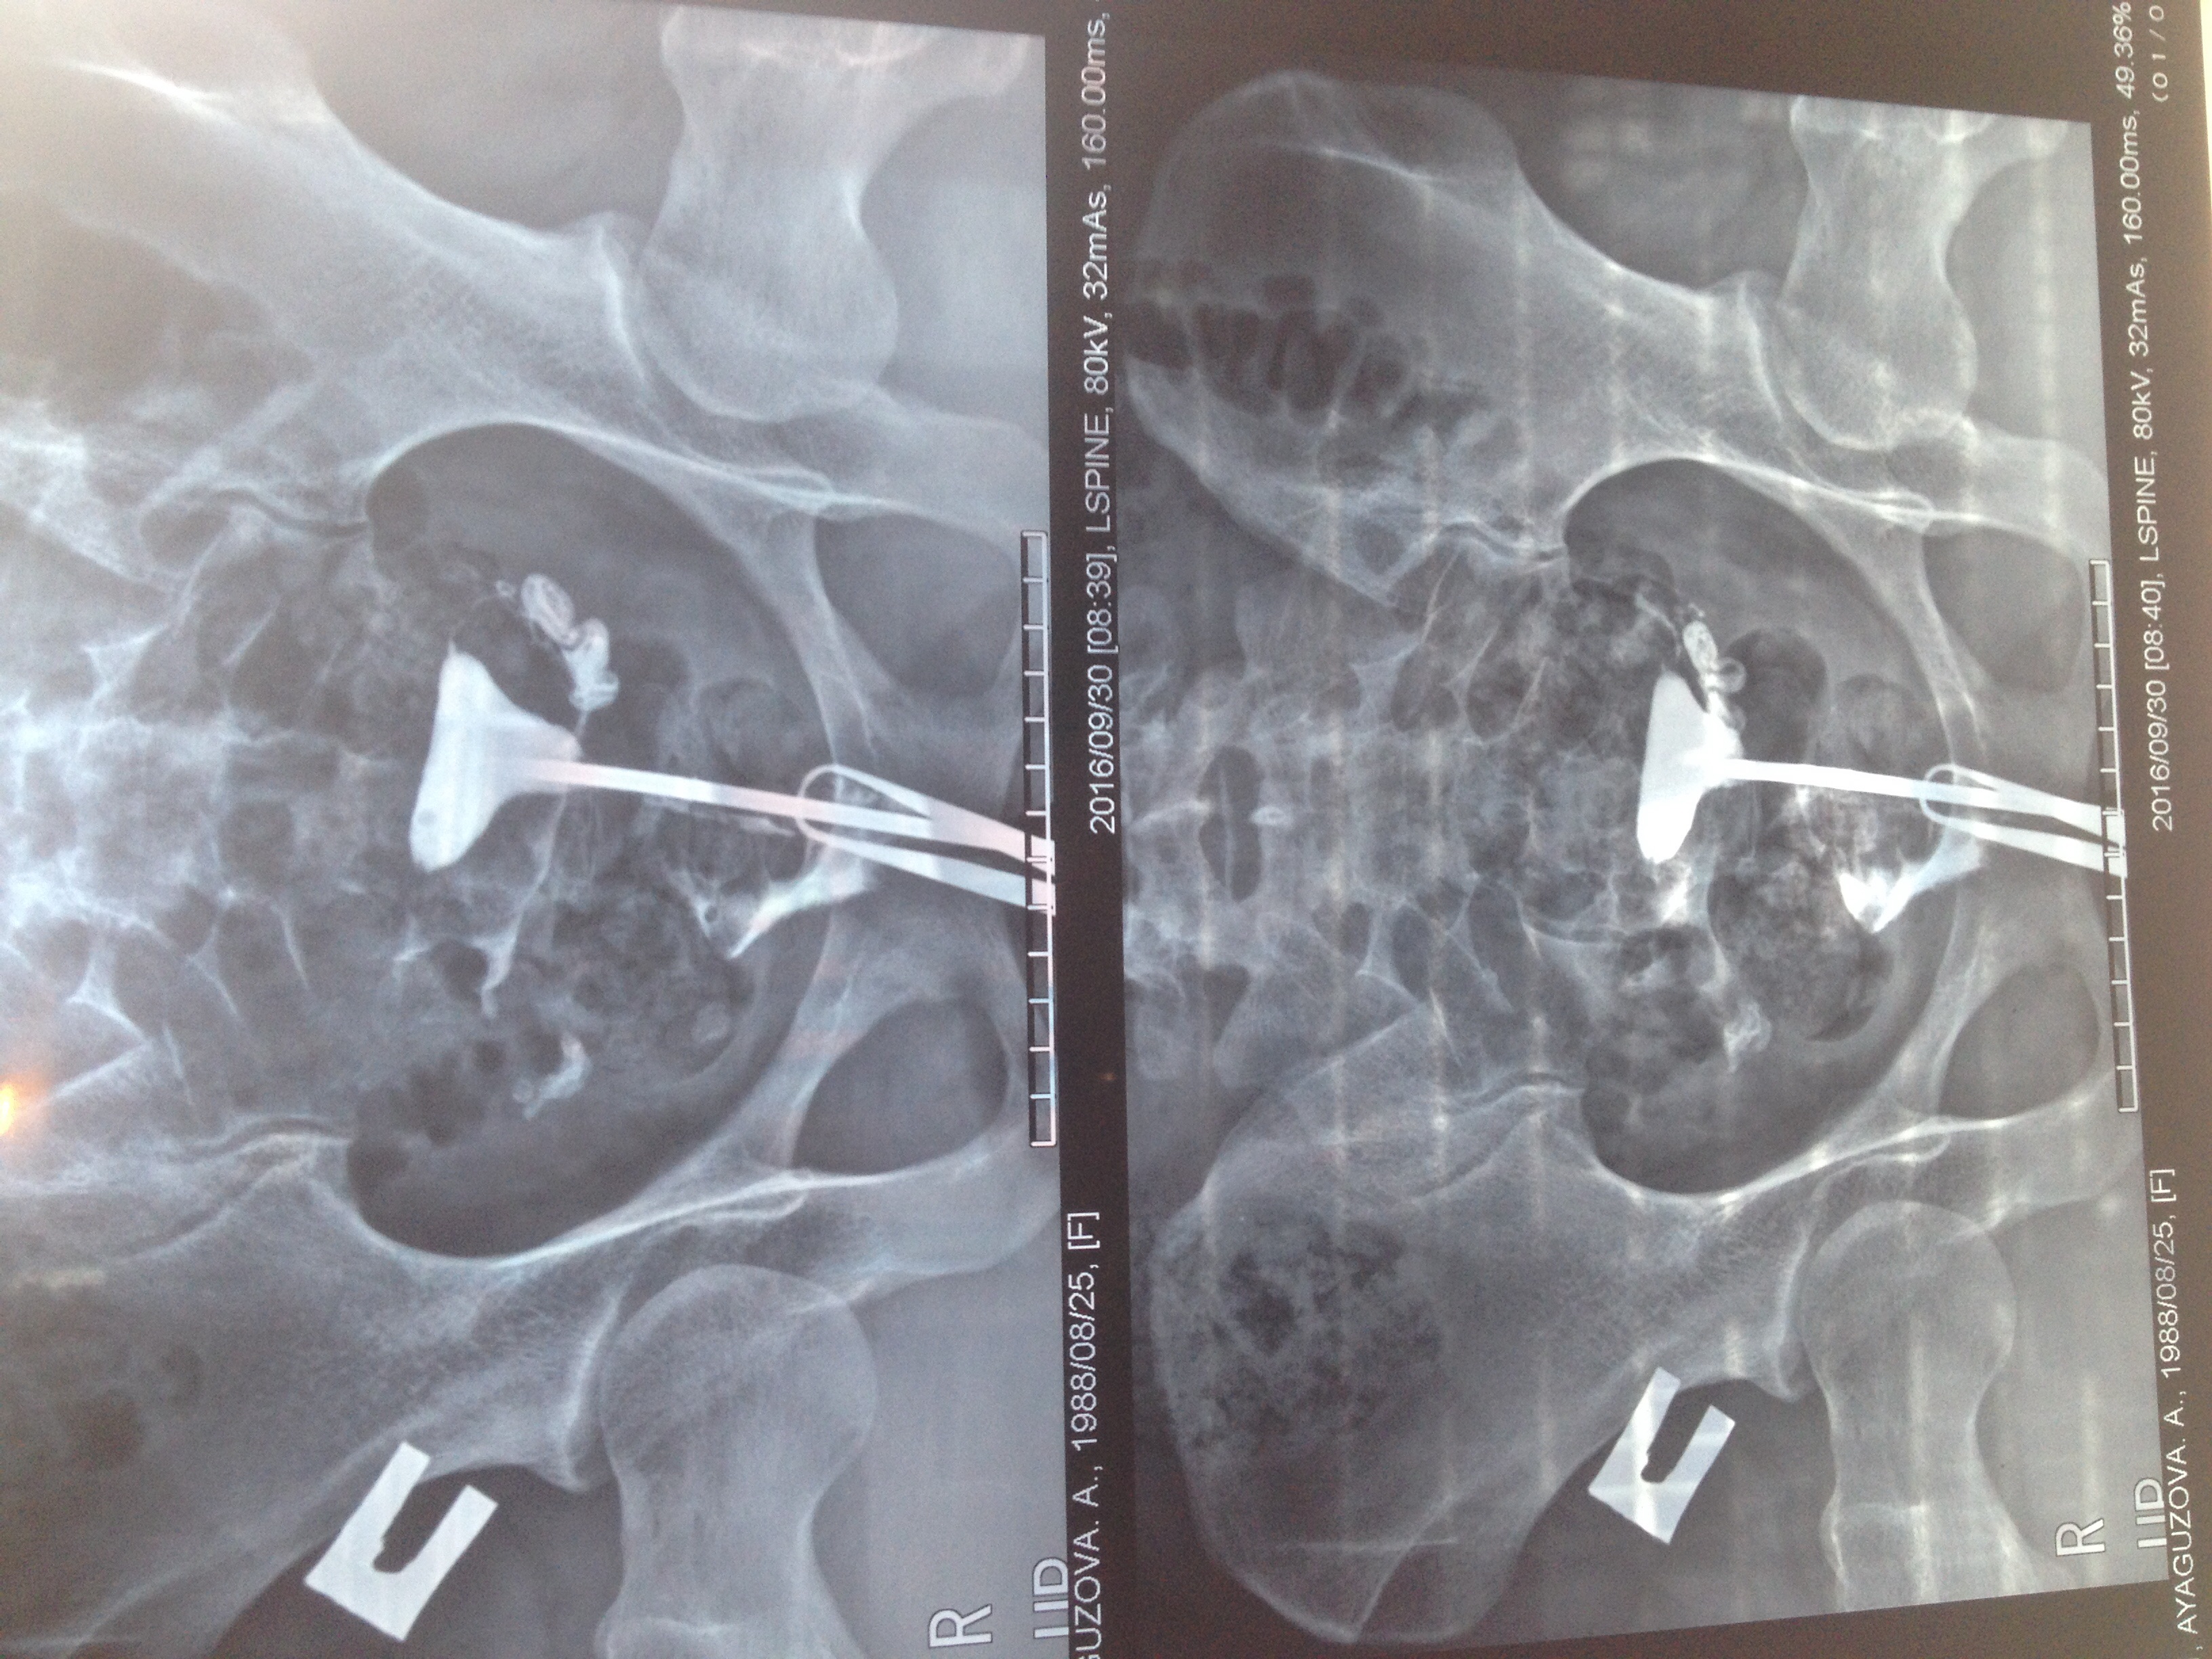

Гистеросальпингография: описание и фотографии